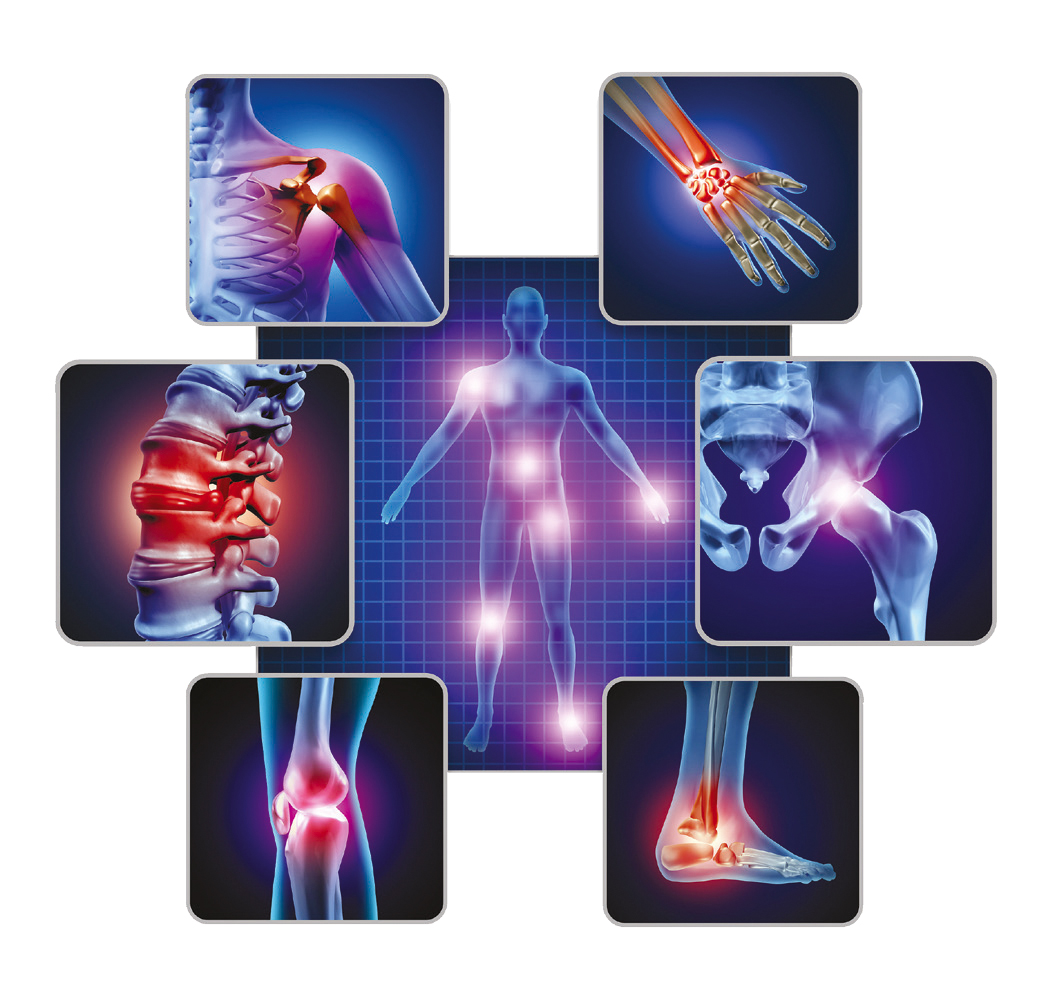

WHAT IS OSTEOARTHRITIS (OA)?

- Osteoarthritis (OA) is known as the most common chronic disease of the cartilage. As the cartilage breaks down due to wear-and-tear and/or mechanical stress, it causes swelling, pain and inflammation, leading to extracellular matrix (ECM) loss¹ .

- Knee osteoarthritis (KOA) is a progressive joint disease that often involves intra- and per articular structures² and is considered pathology characterized by articular cartilage lesions, synovitis, subchondral sclerosis, and osteophytes³.

- Knee osteoarthritis (OA) is most often a slowly progressive joint disorder characterized by cartilage degeneration and inflammation⁴. Knee OA commonly results in knee pain and decreases patients’ mobility (e.g. walking and stair climbing)⁵.

- The pain of osteoarthritis is usually related to activity. For osteoarthritis of the knee (Fig. 1), activities such as climbing stairs, getting out of a chair, and walking long distances bring on pain. Morning stiffness usually lasts less than 30 minutes.⁶ Patients often note that their knees “give way,” a so-called instability symptom.

OSTEOARTRİT (OA) SYMPTOMES

The joint pain of OA typically is described as being exacerbated by activity and relieved by rest. More advanced OA can cause pain at rest and during the night, leading to loss of sleep that further exacerbates pain.